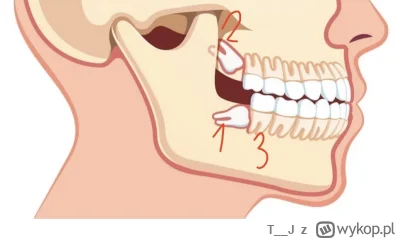

Masz zęba:

1 całkiem zatrzymanego

2 częściowo zatrzymanego

3 rosnącego normalnie ?